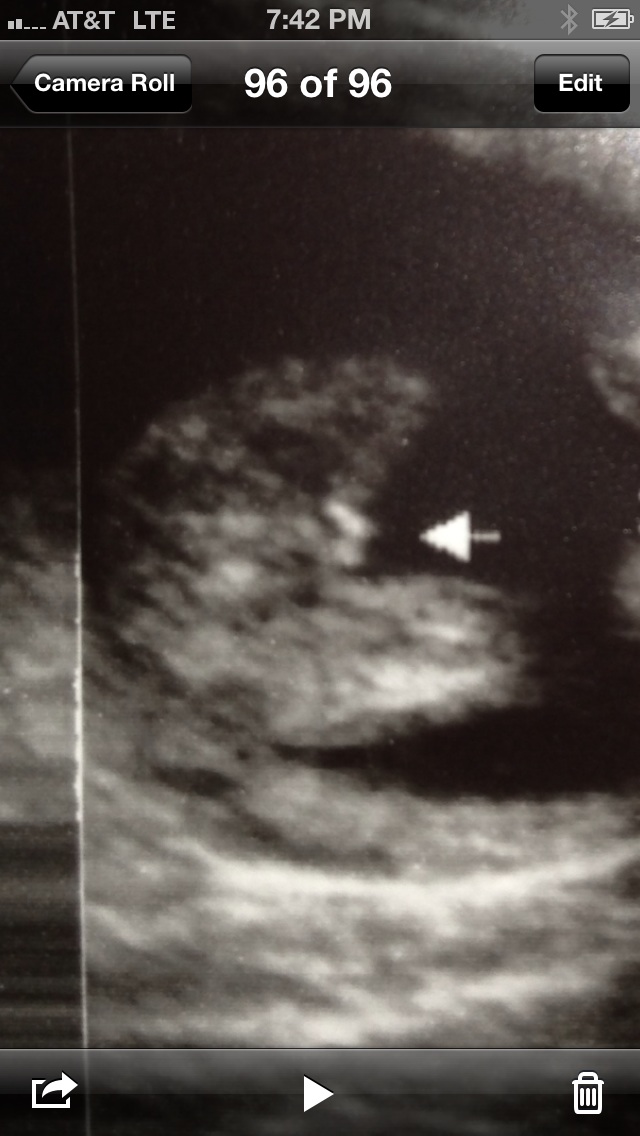

15 week scan is this a girl?